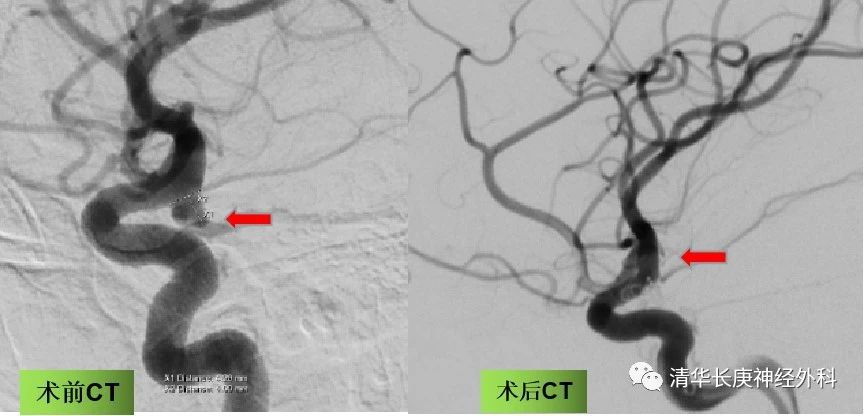

36岁的王女士,突发头痛、头晕10小时余,症状持续不缓解,后就诊于我院急诊,行脑血管CT成像,可疑右侧后交通动脉动脉瘤,紧急行全脑血管造影,术中确认为后交通动脉起始段动脉瘤,开颅手术夹闭风险较高,经与家属沟通后行支架辅助弹簧圈动脉瘤栓塞术,手术过程顺利,患者术后1天恢复良好,无明显神经功能障碍,生活基本自理。动脉瘤是颅内的定时炸弹,一旦破裂,患者有生命危险,目前研究显示开颅和介入手术都取得了不错的临床效果,无论哪种办法,具备手术指征的患者应积极治疗。

图4 手术前后脑血管造影,提示动脉瘤栓塞满意